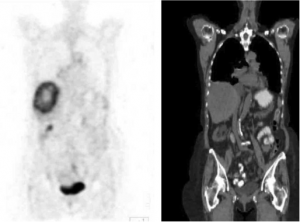

PET-CT הוא כלי חשוב לברור גרורות בכבד מכיוון שמרביתן קולטות FDG, קליטה שהיא אבחנתית לתהליך שאתי בכבד (תצלום 38.10). ה- PET עוזר גם בהגדרת מרחב המחלה בכבד. כל חולה המועמד לכריתת כבד צריך לעבור בדיקת CT תלת פאזי ו- PET-CT להערכת נגעים בכבד ולחיפוש נגעים מחוץ לכבד. רגישות ה- PET-CT היא כ- 90% והדיוק כ- 85%. כימותרפיה טרום ניתוחית מורידה את רגישות בדיקת ה- PET באופן משמעותי.

| תצלום 38.10: שני תצלומים משמאל - ב- CT נראה פגם מילוי בכבד. שני תצלומים מימין - הפגם "נצבע" על ידי FDG ממצא המעיד על תהליך פתולוגי בכבד. | |

|---|---|